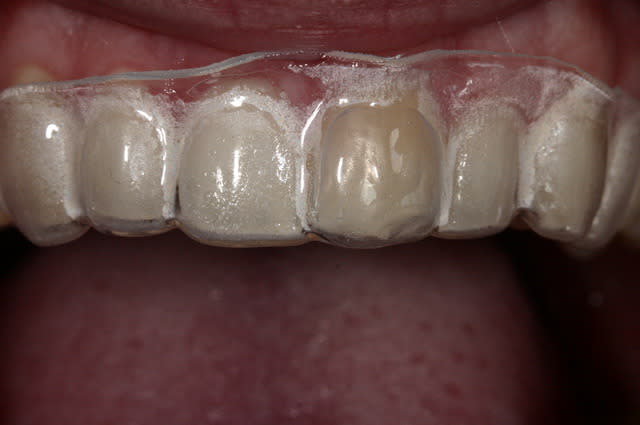

Tu peux faire une gouttière unitaire et utiliser du peroxyde de carbamide à 15% (et pas acid) en port nocturne.

Exemple d'un cas.

Img 9016 vmveq2 - Eugenol

Img 9020 hbsntd - Eugenol

Img 9022 fnap0p - Eugenol

Img 9132 emw9hu - Eugenol